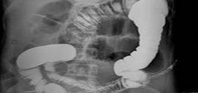

Dr.camscope電(diàn)子(zǐ)肛✘"↔腸鏡

治療腸炎,首先要(yào)搞清楚病情,然♠₹ 後才能(néng)對(duì)症治療。醫(yī)院采用(yòng)電(d$✔σ∏iàn)子(zǐ)肛腸鏡為(wèi)患者确診。₹↕π£該設備是(shì)目前國(guó)際公認較為(wèi)優秀的(§πde)肛腸成像檢查系統。可(kě)對(duì)肛ε≠λ腸內(nèi)部深層病竈部位進行(xíng)圖÷ ✘♣像采集,讓醫(yī)患雙方都(dōu)能(néng)清晰、、直觀地(&↔♦dì)了(le)解病情。